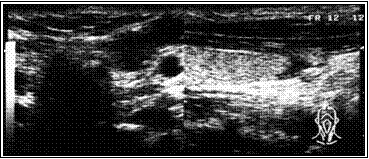

На приведенных ниже эхограммах демонтрируется динамика регрессии в течение года.

В. Эхограмма через год после склеротерапии. Полная регрессия узла.